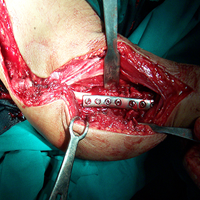

Imm Post-op

Best Orthopedic Surgeon In Satellite|Orthopedic Oncology Doctor